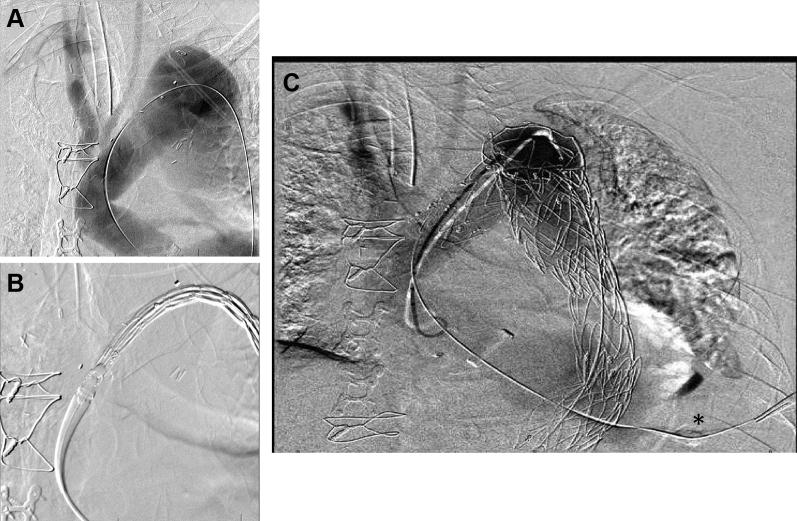

Thoracic endovascular aortic repair (TEVAR) provides an alternative to open surgery for a variety of aortic diseases. However, complex anatomy and previous operations may preclude traditional approaches to TEVAR. Percutaneous transapical access through the left ventricle is a feasible option to facilitate externalized "rail" wire support for complex TEVAR. We present the case of TEVAR for a residual type B aortic dissection facilitated by percutaneous transapical access.